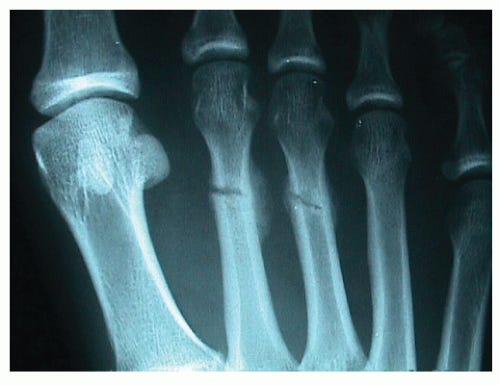

“Fell down the stairs. Fractured my third metatarsal.”

Meanwhile, the foot doctor visits continue, sometimes twice a week, where he X-rays my progress and retapes my cast. The bruises on my foot turn from blue to green to yellow. I never run into the woman with the fractured ankle again, but I think about her a lot. All the time, actually.